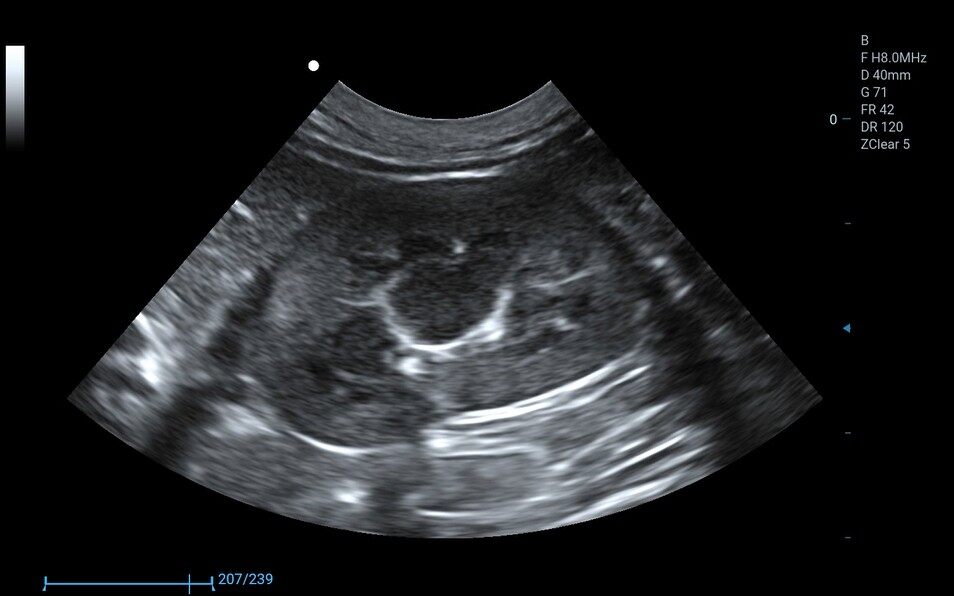

6C1PD ● 3.5-12.0MHz ● Micro convex array probe ● For Abdomen, Cardiology, Reproduction |

3C5PD ● 1.0-7.5MHz ● Convex array probe ● For Abdomen and Reproduction |

10L2PD ● 4.2-16.0MHz ● High-frequency linear array probe ● For Abdomen and Small Parts |

7L4PD ● 4.2-15.0MHz ● Linear array probe ● For Abdomen and Small Parts |